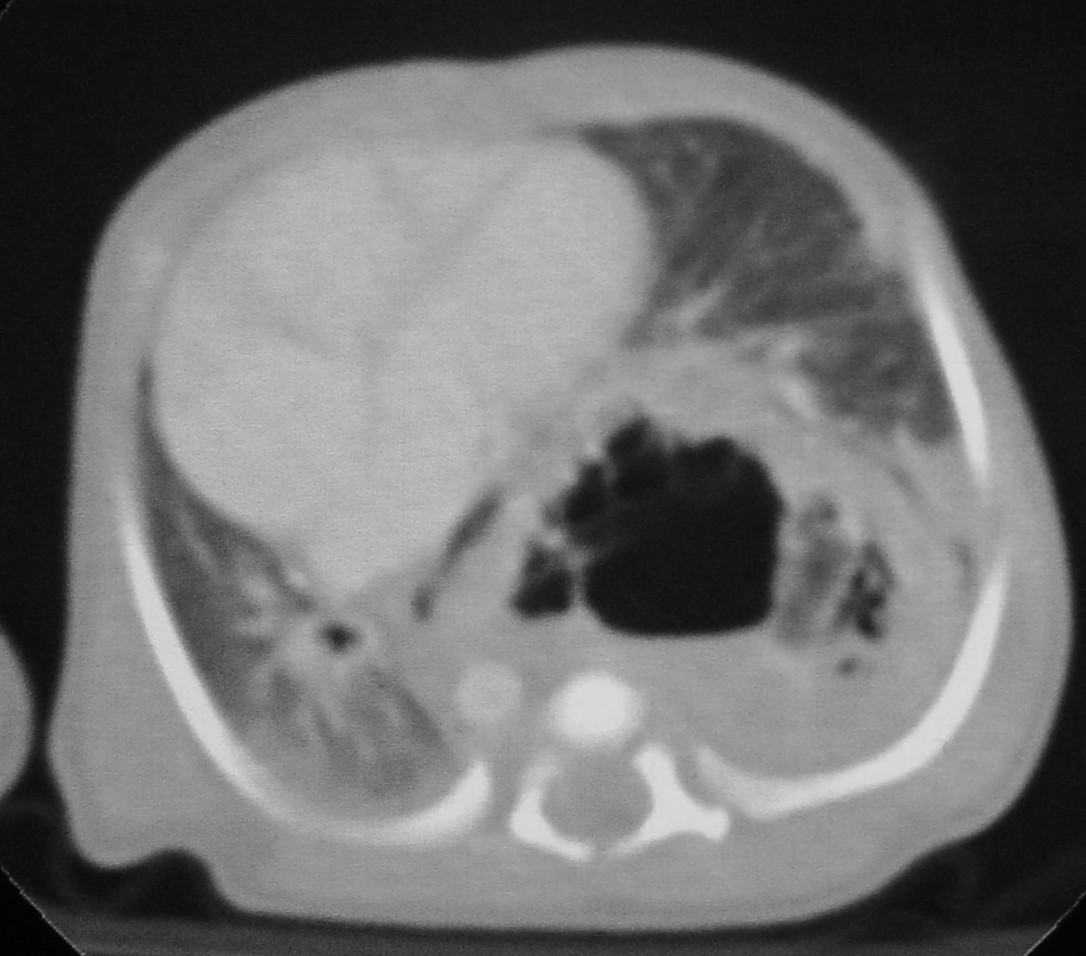

L. � un neonato di un giorno di vita e presenta distress respiratorio secondario a deviazione del mediastino da massa toracica sinistra. In diagnosi prenatale veniva individuata una lesione macrocistica compatibile con CAM tipo 1. Nel corso del secondo trimestre di gravidanza si assisteva a comparsa di deviazione mediastinica, con peggioramento della compressione a fine gravidanza (Figura 6)

In seconda giornata di vita veniva eseguita una lobectomia superiore sinistra. Il decorso � stato privo di complicanze (Figura 7 e Figura 8). Controllo post operatorio a 1 mese (Figura 9).